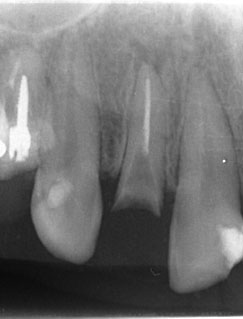

レントゲンで見ても、右上2では歯質が歯肉縁上にのこっていない。しかし歯根は長いのでMTMの適応症例です。

| 治療前で歯根が長いのがわかります。歯根がある程度長く無いと、MTMは行えません。 | MTM終了時のもの。フックが上の金属に接している。また根尖に透過像があるが、歯が動いた証拠です。 |